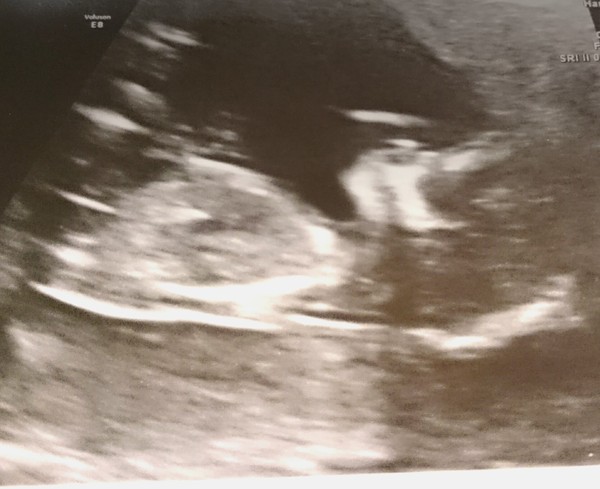

Thanks Lovelybeano! Scan went well! They've moved me forward a day so I'm 12+6 and EDD is now 16.6.16 - Awesome date! Very very happy. Can't wait to finally tell my family this weekend!!

That dates brill!! Lovely scan pic, glad it all went well!! Have you thought about how you're going to tell family?

Thanks all 😀 lovely scan pic Emma! kezod dry blAnd things work well for me, especially salty things... I'm enjoying salted popcorn at the minute... Drinks wise it's hit and miss... Lots of the women on the HG forum swear by the juice from tinned fruit, I couldn't stomach it, prefer ice cold water.... If it gets bad see go for meds! Xxx

What a lovely scan pic emma congratulations!

Lovely scan pic Emma

fab scan pic so happy it went well Emma!!!

emma - great news about the scan! Its so nice being able to tell everyone :)

Lovely scan emma and really glad to hear your news amy